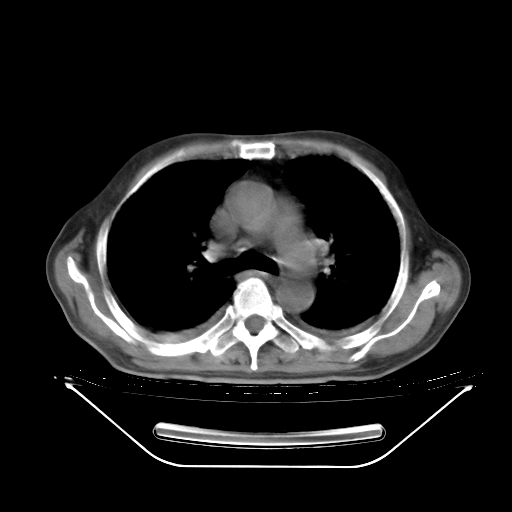

今天复查肺部CT,发现双肺广泛磨玻璃样改变。所以我把3月19日和5月9日相隔50天的肺部CT上传。请大家会诊。

5月9日肺部CT(在4月27日齐鲁医院肺部CT描述部分肺组织磨玻璃样改变,12天后肺组织广泛磨玻璃样改变)

大致读了系列胸部CT:纵隔窗无明显异常,肺窗:从4、27至今:主要是双肺中下野外带可见毛玻璃样改变,目前处于急性肺泡炎阶段,至于原因考虑1、结替组织或胶原血管性疾病所致?2、恶性疾病如恶组在肺部所致的表现或细支气管肺泡癌?3、药物或其它原因如肺蛋白沉着症所致肺泡炎目前不太可能?总之,明天就去请我院的呼吸科、感染科、血液科和临免专家会诊哈。